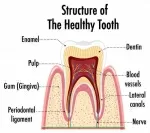

Требуется ли удаление нервов согласно снимку?

Меня беспокоит боль в 4-ом и 5-ом зубе. Боль очень похожа на пульпитную. Сделала снимок. Стоматолог сказала, что сильное воспаление. Необходимо удалять нервы в 4-ом и 5-ом зубе. После этого консультировалась с другим стоматологом и тоже делала снимок, и по нему зубы здоровы, подозревают невралгию. Мне никак не дает покоя первая консультация, может все-таки зубы дают такую боль.

Требуется ли удаление нервов согласно этому снимку?

По приложенному снимку определить необходимость удаления зубов невозможно. Необходим в первую очередь клинический осмотр, далее, при наличии полостей или повреждений эмали делают рентгеновский снимок для оценки глубины поражения. Как минимум начать стоит с ортопантомограммы. Сейчас судить невозможно, так как на снимке могут быть артефакты.